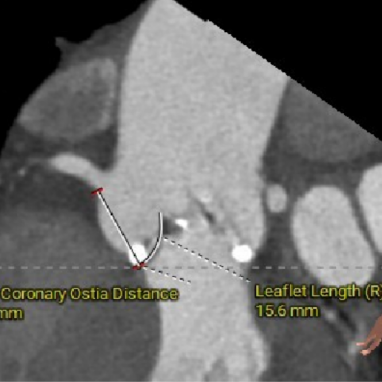

● 左右冠脉开口高度可,左冠切线角度测量瓣叶大于LCA开口下缘到根部距离;

LCA&LEAFLET

图片

RCA&LEAFLET

术前考虑右侧股动脉为主入路,左侧为辅助入路。非横位心,主动脉弓角度、宽度尚可,预估输送器过弓难度适宜,跨瓣难度适宜,术中必要时采用Snare辅助。左右冠脉开口高度可,左冠切线角度测量瓣叶大于LCA开口下缘到根部距离,结合瓦氏窦及STJ尺寸预估,冠脉风险适中,建议术中密切关注左冠灌注情况。外周入路走行适宜,腹主中下端和左右髂总散在钙化,血管内径尚可,血管内壁存在不规则纤维增厚和钙化斑,入路穿刺规范操作,小心通过,避免入路血管损伤及相关并发症。重度钙化二叶式病变重度主动脉瓣狭窄,其瓣口面积小,瓣口限制明显,术中瓣膜锚定难度较大,瓣膜植入受二叶瓣瓣叶及团块状钙化挤压存在移位及少量偏多瓣周漏风险,为避免手术并发症,手术预装AV26瓣膜,根据20mm球囊预扩结果选择瓣膜型号,计划瓣膜瓣上3mm开始释放。